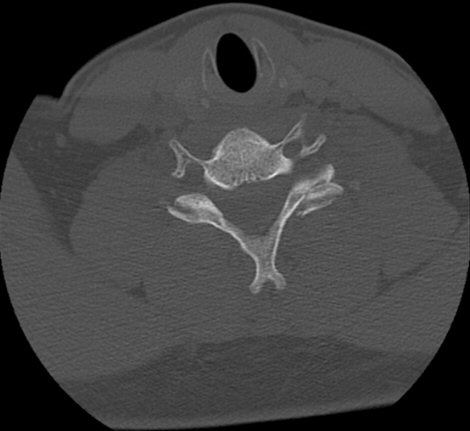

Skada: Luxation facettled C3-C7

Facettledsluxation C6 vänster. Hade även fraktur. Reponerades och opererades.